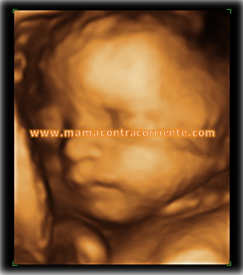

He tardado casi un mes en publicar esta entrada. Es el tiempo que he tardado en ponerle a la foto que más me gusta una marca de agua que fuera lo suficientemente molesta para estropear la foto pero, al mismo tiempo, lo suficientemente pequeña para que se pudiera apreciar al chiquitín. ¡Mis sudores me ha costado!.

Hay quien dice que lo de 4D está mal dicho porque no existen cuatro dimensiones. Bueno, se sobreentiende que son tres dimensiones más el movimiento. Aunque para quien no se la haya hecho hay que explicar que el movimiento lleva un pelín de retardo… Se ve muy claramente pero si el niño se mueve mucho en ese momento, la imagen se enturbia por unos momentos.

Lo bien o mal que se capte la imagen depende de varios motivos. Yo tengo la suerte de que se me ve muy bien, la ecografista siempre me ha dicho que tengo una musculatura estupenda en esa zona. Se supone que una persona con mucha grasa, por ejemplo, tendría más dificultad para la visualización, pero yo conozco mujeres delgadísimas a las que no se les ha visto nada bien. La posición del bebé también influye, lógicamente. Si ese día está girado o se tapa con las manos, normalmente hay poco que hacer.

Se suele realizar entre las semanas 24 y 30 aunque las semanas idóneas son entre la 26 y la 28. Se considera que antes de esas semanas el bebé tiene muy poca grasa corporal por lo que su carita no es del todo definitiva (de esto doy fe porque al mayor le vimos con 20 semanas y tenía la carita muy chupadita) y pasada la semana 30 están tan apretados en la bolsa que la cara puede salir deformada (nariz aplanada, por ejemplo). Yo, las dos veces, me la he hecho durante la semana 27.

Como he dicho antes, hacérsela o no es una decisión muy personal. Para nosotros ha marcado en ambas ocasiones un antes y un después. Por mucho que notes a tu bebé, verle en movimiento, ver su cara, verle abrir la boca, tragar líquido amniótico, cogerse un pie, chuparse un dedo, quitarse el cordón de la cara, sonreir, responder a los movimientos del ecógrafo… es impresionante. Sales de allí creyéndote mucho más el embarazo y siendo plenamente consciente de la vida que tienes en un interior.

En nuestro caso, además, esta ecografía nos ha servido para tener un déjà vu (o como se escriba). Son tan idénticos que costaba creerlo cuando empecé a verlo en pantalla. Quizá este pequeñín esté un poco más mofletudo, pero por lo demás, dos gotas de agua. Incluso en las mediciones, el tamaño de su abdomen salía más pequeño que el resto del cuerpo, exáctamente igual que su hermano. Vaya, que teníamos el molde de hacer niños bien conservado.